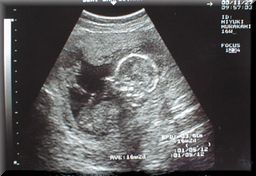

00/10/22 11週目 | ![]() | 4.6cm |

・油の匂いで気持ちが悪くなる。 天ぷら料理の時は、お父さんに揚げてもらう。 ・食事後の皿洗いは、お父さんと千佳に手伝ってもらってます。 ・夜中に急に気持ち悪くなり、嘔吐したこともあった。 ・千佳の時より、つわりはひどいような気がする。 |